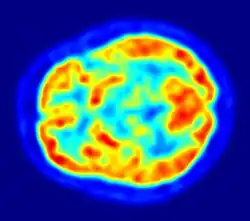

Embora o cérebro humano represente apenas 2% do peso corporal, ele recebe 15% do débito cardíaco, 20% do consumo total de oxigênio do corpo e 25% da utilização total da glicose corporal.[17] O cérebro usa principalmente glicose para energia, e a privação de glicose, como pode acontecer na hipoglicemia, pode resultar em perda de consciência.[18] O consumo de energia do cérebro não varia muito ao longo do tempo, mas as regiões ativas do córtex cerebral consomem um pouco mais energia do que as regiões inativas, o que constitui a base para os métodos de neuroimagem funcional de PET e fMRI.[19] Essas técnicas fornecem uma imagem tridimensional da atividade metabólica.[20] Um estudo preliminar mostrou que os requisitos metabólicos do cérebro em humanos atingem o pico por volta dos cinco anos de idade.[21]

Imagiologia

As técnicas de neuroimagem funcional mostram mudanças na atividade cerebral que se relacionam com a função de áreas cerebrais específicas. Uma técnica é a imagem por ressonância magnética funcional (fMRI, sigla em inglês), que tem as vantagens sobre os métodos anteriores de SPECT e PET de não precisar do uso de materiais radioativos e de oferecer uma resolução mais alta.[37] Outra técnica é a espectrografia funcional de infravermelho próximo (fNIRS). Esses métodos baseiam-se na resposta hemodinâmica que mostra mudanças na atividade cerebral em relação às mudanças no fluxo sanguíneo, úteis no mapeamento de funções para áreas cerebrais.[38] O fMRI em estado de repouso analisa a interação das regiões do cérebro enquanto o cérebro não está realizando uma tarefa específica.[39]